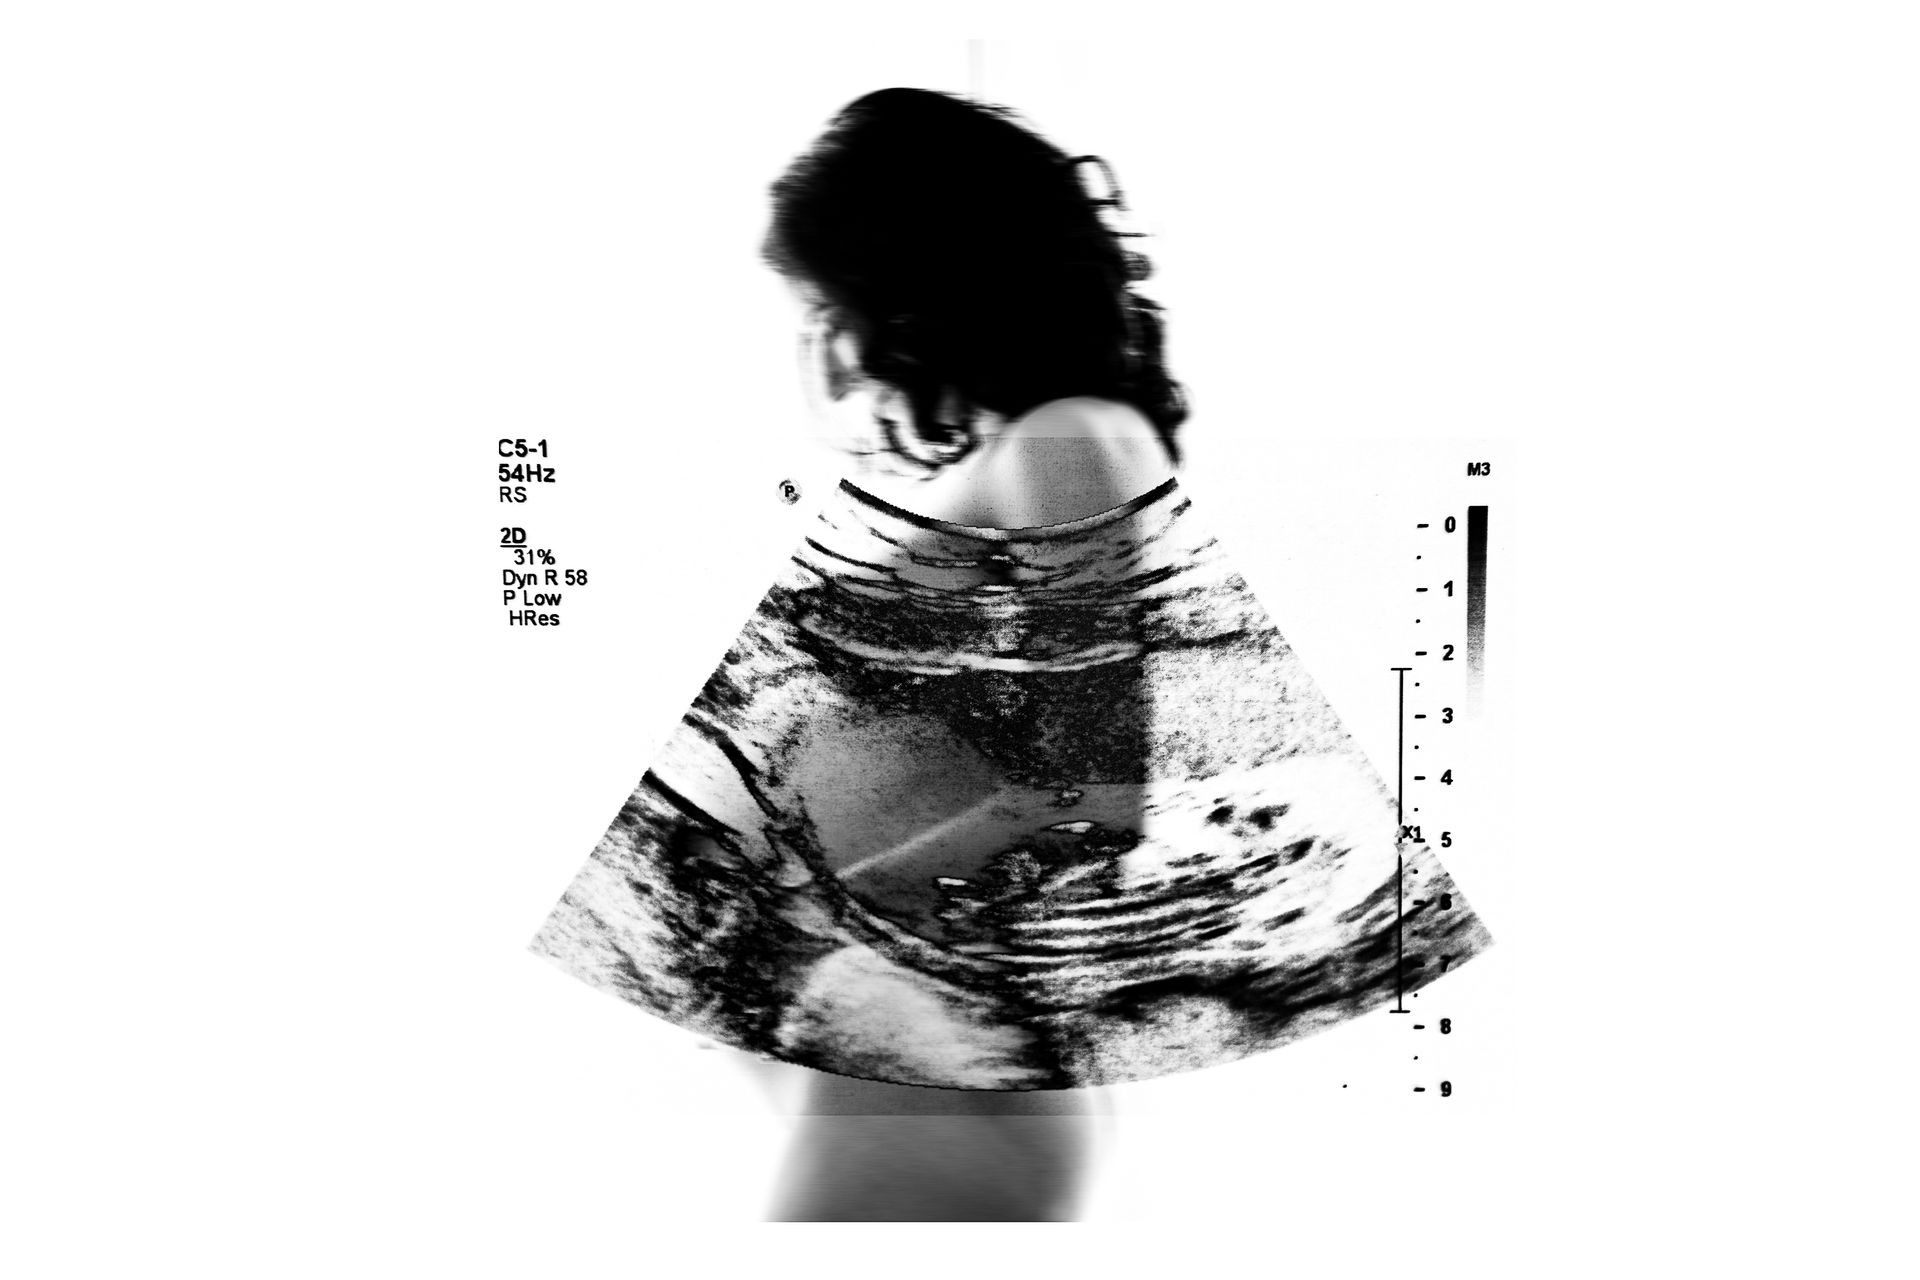

No Brasil, abortos espontâneos são comuns. Cerca de 23 milhões de gestações em todo o mundo terminam em aborto espontâneo a cada ano – isso é 15% do total ou 44 a cada minuto, de acordo com novas estimativas publicadas na revista médica The Lancet em 2022.

Confesso que a perda da Luna, minha filha, foi o princípio de todo esse projeto, a necessidade de validar a sua existência, de me validar como mãe e como mulher que deseja ser mãe, mas o tempo me mostrou que esse projeto vai muito mais além.